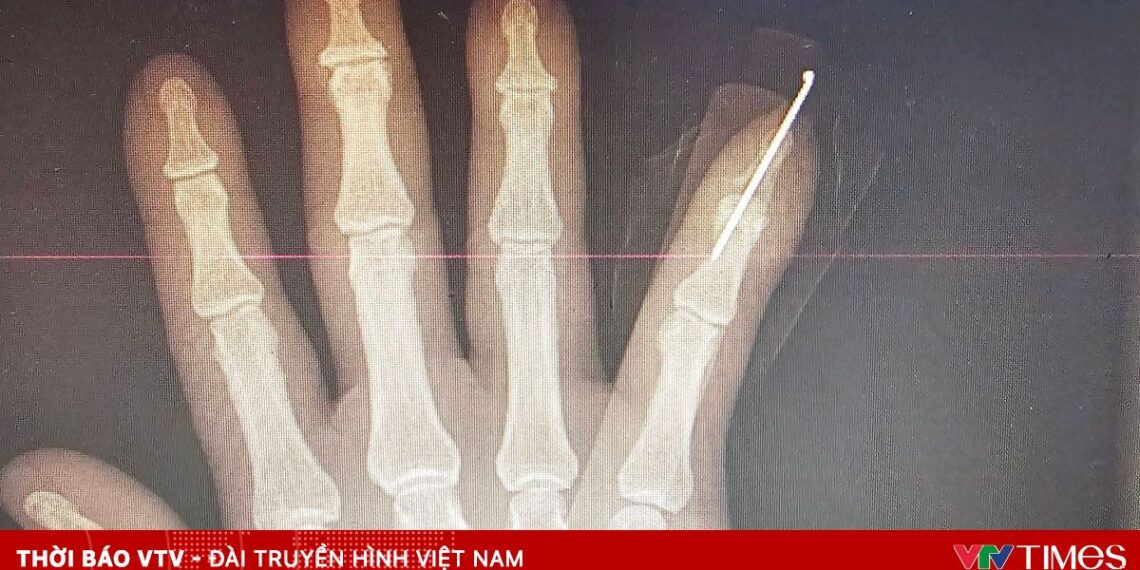

Bệnh nhân là nam giới, 63 tuổi, bị tôn cắt trong lúc làm việc. Khi nhập viện, bệnh nhân trong tình trạng đứt lìa hoàn toàn đốt 3 ngón V bàn tay phải, vết thương sắc gọn, nguy cơ cao mất chức năng bàn tay nếu không được can thiệp kịp thời. Ngay sau khi tiếp nhận, các bác sĩ nhanh chóng đánh giá tổn thương và chỉ định phẫu thuật vi phẫu cấp cứu.

Ekip phẫu thuật đã tiến hành nối xương, gân, mạch máu và thần kinh bằng kỹ thuật vi phẫu chuyên sâu. Ca mổ diễn ra thuận lợi, ngón tay được tái lập tuần hoàn tốt. Sau phẫu thuật, bệnh nhân tiếp tục được theo dõi sát và tập phục hồi chức năng nhằm tối ưu khả năng vận động của bàn tay.